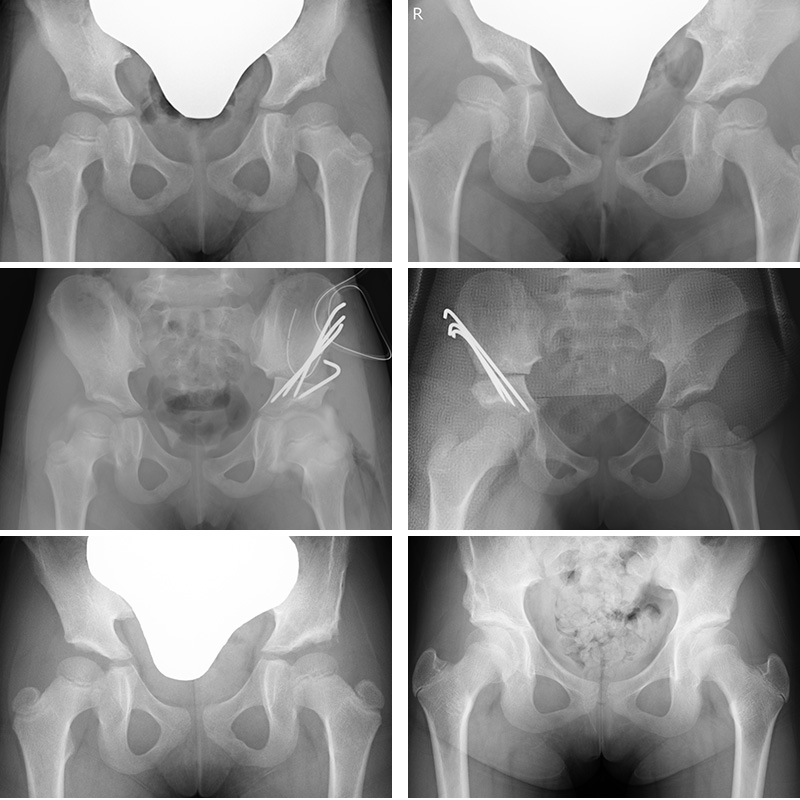

発育性股関節形成不全(先天性股関節脱臼)

生まれつき股関節の形成が不十分,緩いなどの素因に乳児期の生育環境などの要素が加わって股関節が脱臼する疾患です.1970年代の育児方法の啓蒙により発生率は1000人に1-3人と激減していましたが近年では歩行開始後に発見される例も見られ問題になっています。

・治療法 Rb法(3-6か月)

重度でなければ3-6か月の間は主にリーメンビューゲル(Rb)装具を使って整復し,緩めてゆきつつ約3か月の装着を行っています.装着後1-2週間以内に股関節周囲の腫れを伴って整復されることが多く,80%近くは整復できます.合併症の予防のため機嫌が悪いときには一旦外すなど無理をしないようにしています。

Rb装具装着し,整復が得られました

・治療法 牽引療法(7か月-2才)

Rb法で整復位が得られない場合や7か月を越えて診断された場合は入院していただいた上で牽引療法による整復を行います。

牽引は通常6週間行い,最後に全身麻酔をかけて股関節造影と最も股関節が安定する肢位でのギプス固定を行います.ギプス除去後にぶかぶか装具,ホフマンダイムラー装具と2種類の装具を装着しつつ少しずつ股関節を動かしてゆきます.入院期間短縮のため牽引療法の前半を貸し出した牽引装置を用いて自宅で行っていただくHome traction法も行っています。

開排牽引を行っています

股関節造影

整復後のギプス固定

装具を用いて動かしてゆきます

・治療法 観血的整復術

2歳を大きく越えて診断された場合や上記保存療法で整復が困難な場合は手術で脱臼を整復します。岡山大学ではじめられた広範囲展開法を用います。

・整復後の補正手術

整復は得られたものの骨盤側の成長が悪く大腿骨頭の屋根の形成が不十分な場合があります。成長を待機しますが成長終了後に遺残することが予想される場合は,成人期に手術を行うより身体的,社会的に影響が少ない6歳前後で骨盤骨切り術を行って将来的な不安のない股関節を形成します。

ソルター骨盤骨切り術により被覆が改善しました。